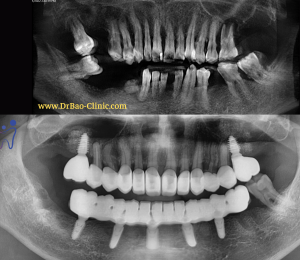

👏Ở tuổi 87, với 6 stent đặt ở mạch vành, thật không quá nếu nói đây là một hành trình tìm lại nụ cười của ông N.X.Đ. Ông đến nha khoa khi răng đã được bọc sứ gần hết, 6 răng thật còn lại cũng bị hư hại nghiêm trọng.

🦷🦷Ông đã làm răng sứ lại 3 lần, nhưng vẫn không ăn uống được, đau nhức, hôi miệng. Răng sứ cứ vài tuần lại long ra phải gắn lại.

– Bị mất kích thước dọc, cắn sâu. Khớp cắn rất nhạy cảm với thay đổi, dù là rất nhỏ.

– Răng sứ hiện tại quá to, và thô, làm dính liền tất cả các răng sứ với nhau, rất khó vệ sinh, dẫn đến viêm nướu nặng.

– Răng thật còn lại thì mòn cổ nặng, có răng nhiễm trùng cần điều trị tủy

Tình trạng răng ban đầu